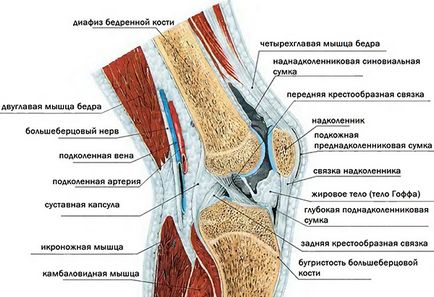

A probléma az előfordulása ödéma közvetlenül kapcsolódik a funkciók és szerkezete a térd.

A stabilitás ebben hajlékonysága lehetővé teszi a szalagok, amely az oldalsó, hátsó és intraartikuláris szalagok. Meniscusok is fontos szerepet játszanak a mobilitás biztosítását. Ez a két ízületi porc felülete. Minden fenti elemek (nem folyékony) van több nyirok- és véredények. Az utóbbi biztosítja a szükséges tápanyag minden szövetben.

A tanulmány a szerkezet a térd lehetővé teszi, hogy jobban megértsék a hatása romboló tényezők